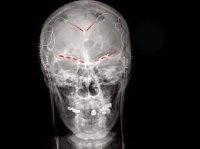

Müasir neyrologiya göstərir ki, ağrı yalnız bədən toxumalarının zədələnməsinə cavab olaraq yaranmır. Beynin anterior singulat korteksi, insula və prefrontal korteks kimi sahələri yalnız fiziki ağrıya deyil, eyni zamanda sosial və emosional itkiyə də reaksiya verir. Yəni, bir dostun itirilməsi ilə əlin yanması beyində oxşar neyron yolları aktivləşdirir. Bu paralellik ağrının təkcə bioloji bir hal olmadığını, onun insan şüurunda bədii və mənəvi simvollaşdığını göstərir. “DogruXeber.tv” üçün yazılmış bu elmi esse, hiss etməyin sadəcə duyumsal deyil, həm də düşüncəvi bir akt olduğunu vurğulayır.